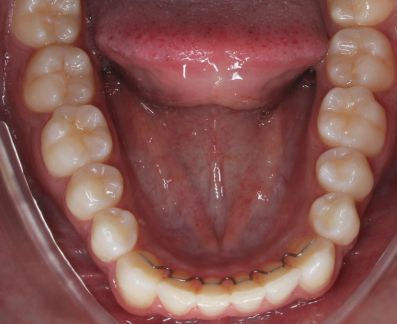

Arco inferior

CLASSE I, DIASTEMA, ARCO ATRÉSICO

Expansão para ampliação do corredor bucal e fechamento de diastemas.